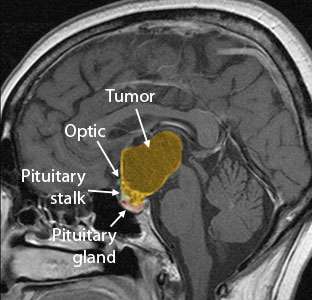

This video shows the endoscopic removal of a craniopharyngioma. The tumor is reached by working over the pituitary gland, taking extreme care to preserve the pituitary stalk. Once the tumor material is removed, the roof of the third ventricle (the deepest area where the tumor was) can be seen. The patient had intact pituitary function and vision after the surgery.

Large craniopharyngioma successfully removed using the Expanded Endonasal Approach.